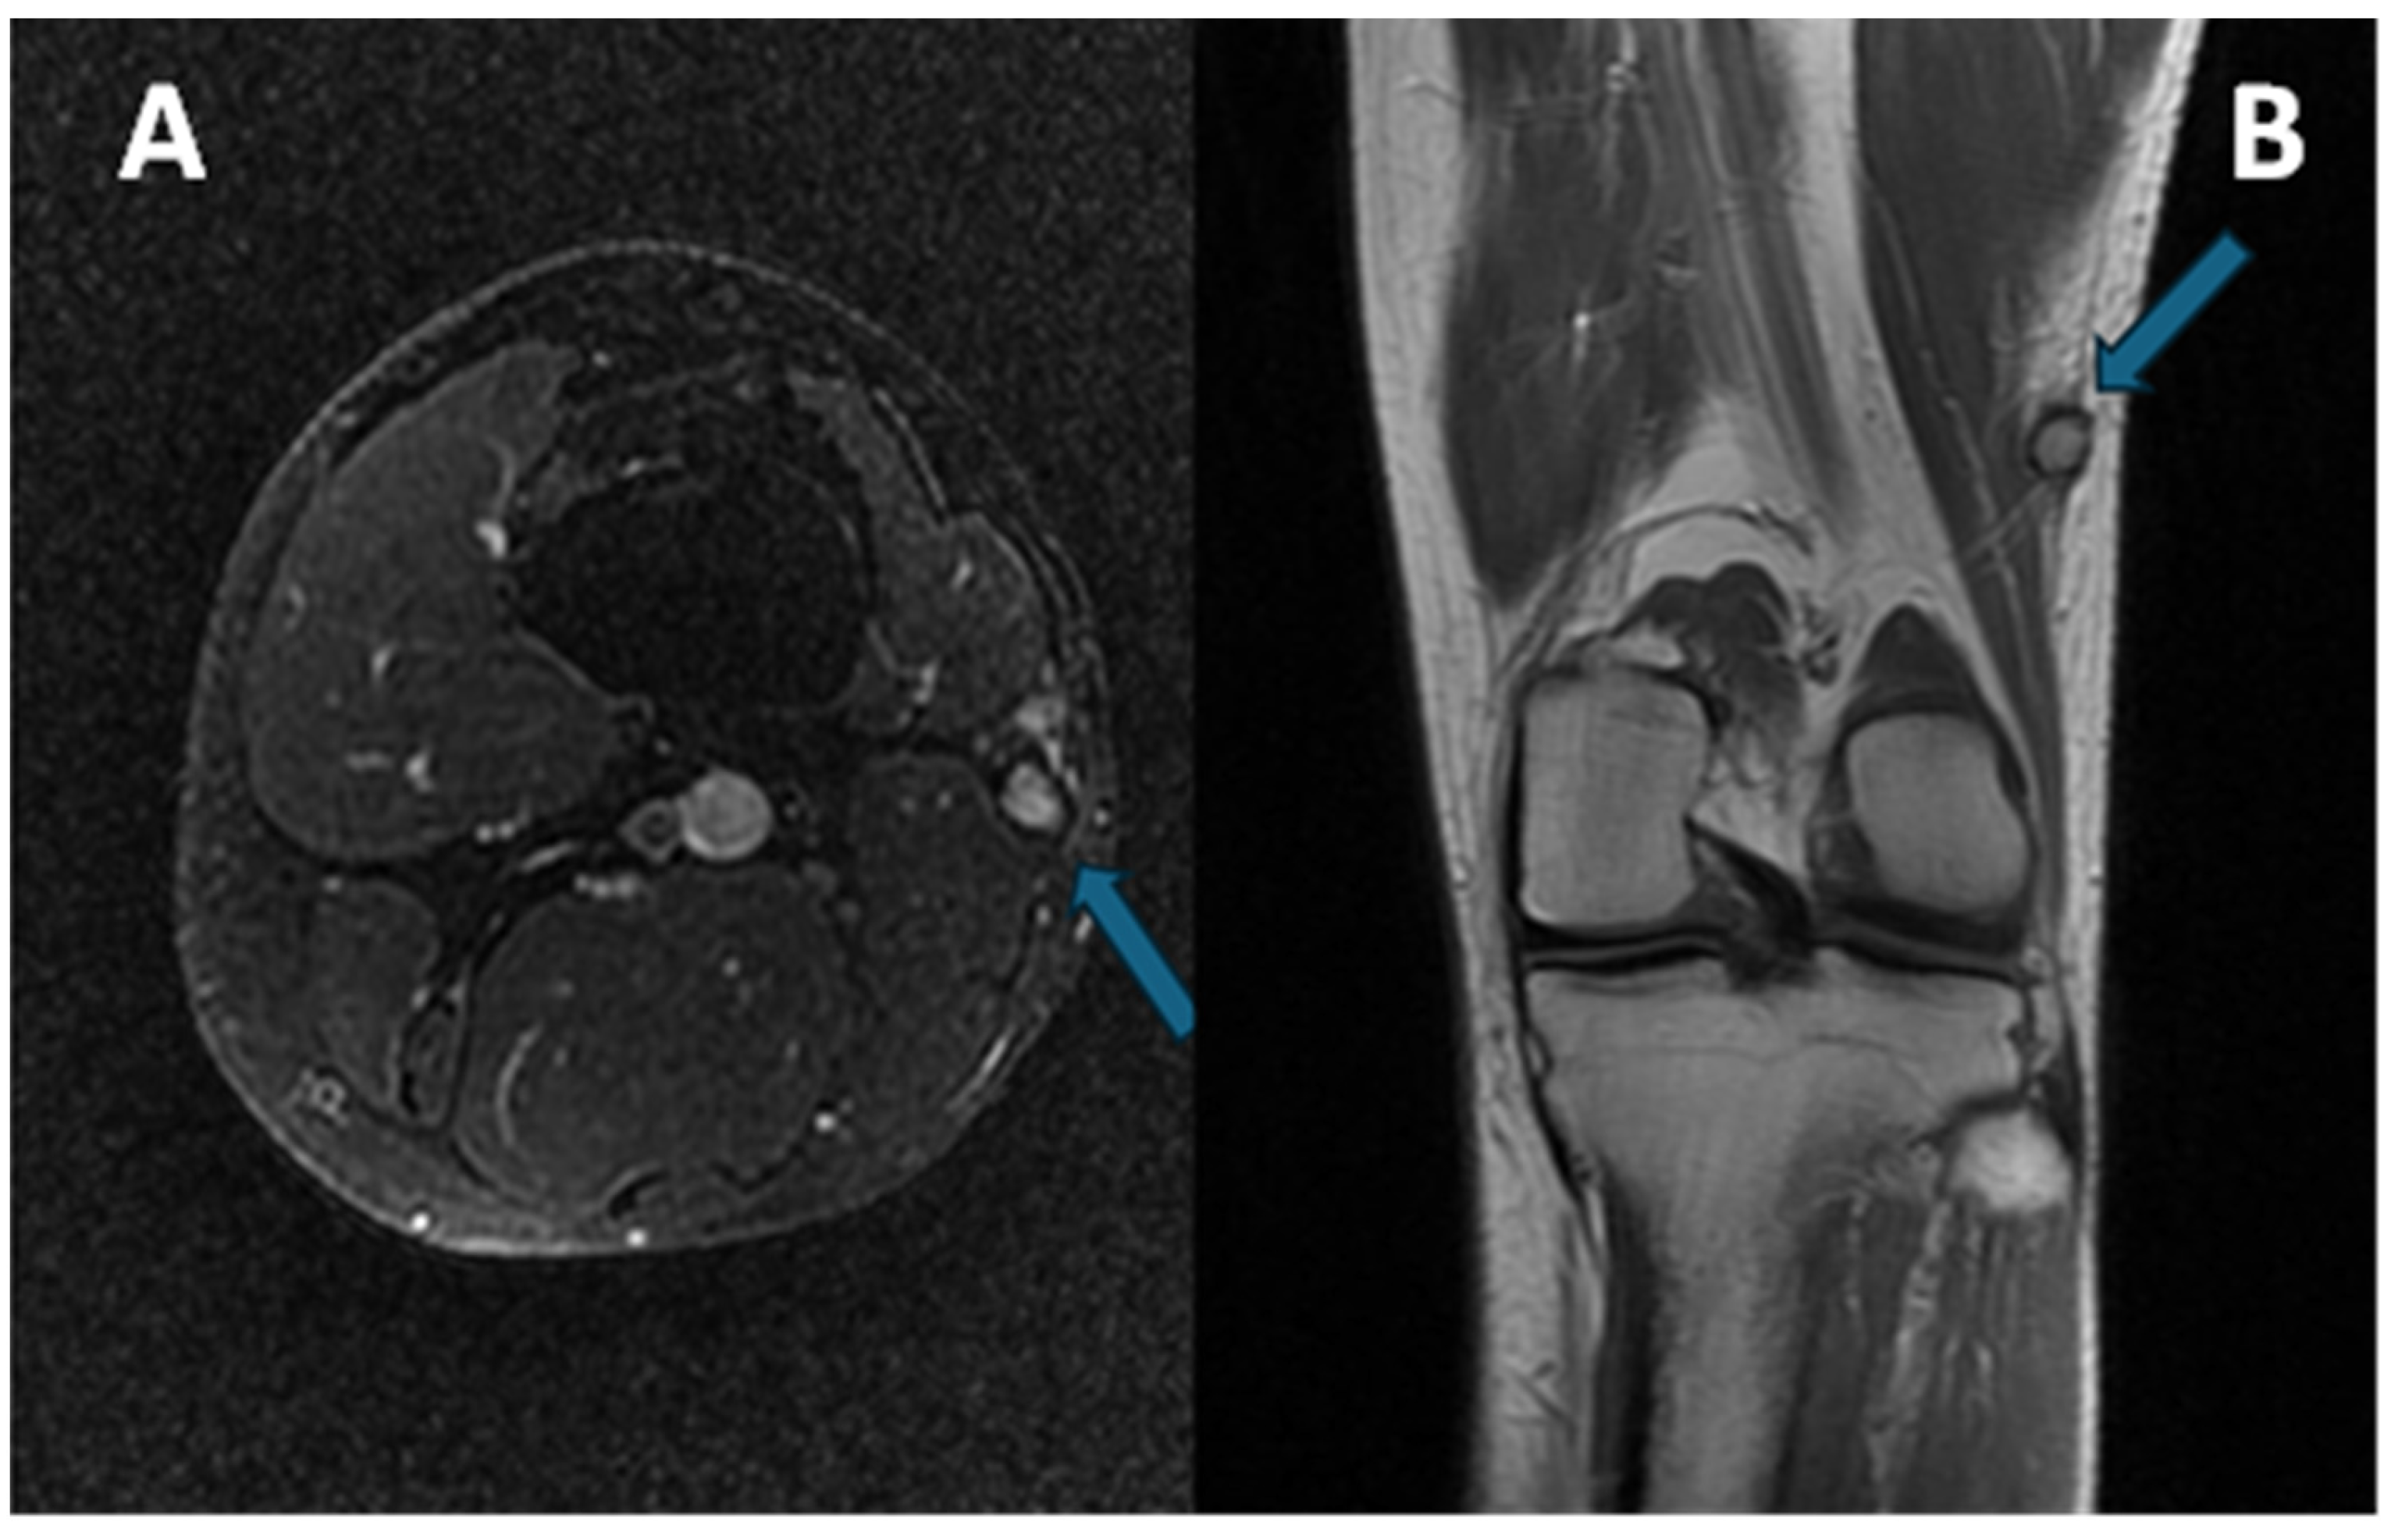

3.4.2. Peritumoral Edema

3.4.3. Other MRI Features